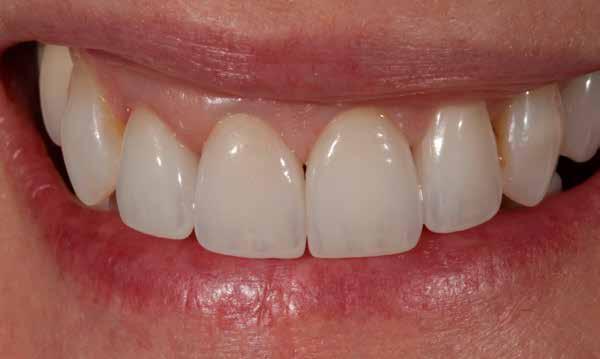

Behelyezés és összefoglalás

A klinikai próba során a hölgy mégis a központi diasztéma teljes zárását kérte, amit korrektúrégetéssel valósítottunk meg. A folysavazást és szilanizálást követően a kilenc héj és a korona adhezív módon, kompozittal került rögzítésre. A régi, jól bevált analóg módszer az új VITA AMBRIA receptnek köszönhetően hatékonyan valósította meg préskerámiával az esztétikus zóna rehabilitációját. A préskerámia természetes transzlucenciája, opaleszcenciája és fluoreszcenciája élő bázist adott az egyéniesítéshez és karakterizáláshoz. A préselés utáni minimális reakciós réteg gyors kibontást és kidolgozást tett lehetővé. A préskerámia robusztussága biztonságot hozott. Az optikai összhatás és összjáték a VITA LUMEX AC leplezőkerámiával hatékonyan segítette a páciensre jellemző finomságok megjelenítését. A hölgy nagyon elégedett volt új mosolyával.

keltett. Az egyébként ideális tipikus formájú koronák esztétikailag optimális gingivakialakítást hoznak létre, a VMK korona kicserélése egyenletes fénytovábbítást tett lehetővé a papilláktól a korona felé és fordítva is. Míg a próba során még minimális sötét approximális háromszögek láthatók voltak, a végleges beragasztásra (Variolink Esthetic, Ivoclar Vivadent) már eltűntek (9. kép). A gingiva tökéletesen hozzásimult az IPS e.max ZirCAD Prime restaurációhoz.

Összefoglalás

Anyagválasztásunk újra tökéletesnek bizonyult. Kiemelkedő természetes hatása folytán akár leplezetlen IPS e.max ZirCAD Prime anyaggal is nagyon jó esztétikai hatású monolit restaurációk készíthetők. Itt az optimális alapot képezte, hogy leplező- és festékanyagainkkal elérhessük a kívánt hatást: hibátlan mosolyt és természetes szépséget. A páciens nagyon elégedett a kezelés eredményével – akárcsak mi magunk (10. kép).